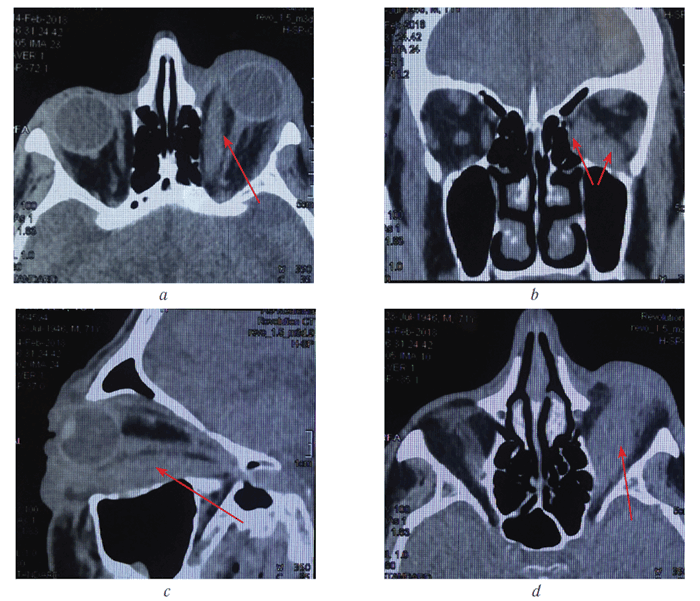

Резко увеличенные нижняя и внутренняя прямые мышцы визуализированы на компьютерных томограммах (рис. 3).

Рис. 3. Компьютерные томограммы орбит того же больного (во всех проекциях визуализируются увеличенные нижняя и внутренняя прямые мышцы (указаны стрелкой); c — визуализируется увеличенная нижняя прямая мышца на всём протяжении от зоны прикрепления к склере до сухожильного кольца

Fig. 3. Computer tomograms of patient's orbits (in all projections, enlarged lower and inner rectus muscles are visualized (indicated by an arrow); с — an enlarged lower straight muscle is visualized from the attachment zone to the sclera to the tendon ring

Fig. 3. Computer tomograms of patient’s orbits (in all projections, enlarged lower and inner rectus muscles are visualized (indicated by an arrow); с — an enlarged lower straight muscle is visualized from the attachment zone to the sclera to the tendon ring